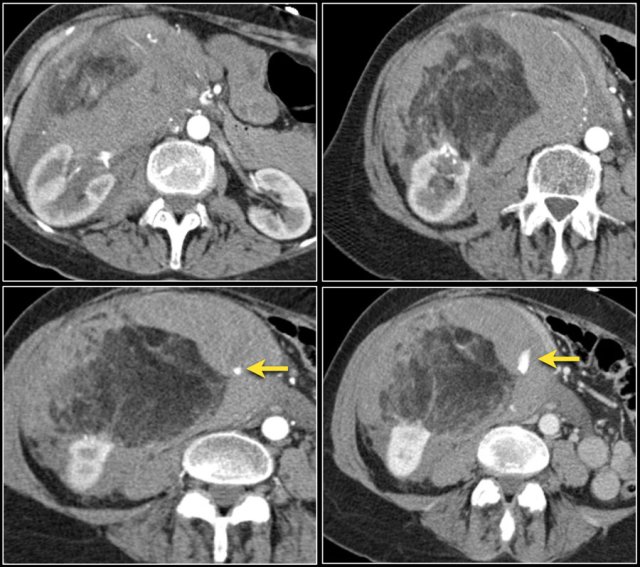

A typical feature of clear cell carcinoma is strong enhancement in the corticomedullary phase.

This can be difficult to assess when the lesion is small and located in the renal cortex, which also enhances strongly.

The nephrogenic phase is therefore the most sensitive phase for the detection of these lesions, as the renal parenchyma enhances homogeneously and more intensely than the tumor (figure).

Here is another case.

In the nephrogenic phase one could argue there is a lesion in the left kidney.

In the corticomedullary phase however it is clear that this is a pseudotumor.

The corticomedullary phase 25-40 sec post injection is strongly recommended. It helps to differentiate tumor from pseudotumor and to assess enhancement of a lesion.

In this phase however a tumor located in the renal medulla can have the same attenuation as the surrounding parenchyma (figure).

Therefore the nephrogenic phase (±100 sec post injection) is the most important phase for the detection of a tumor.